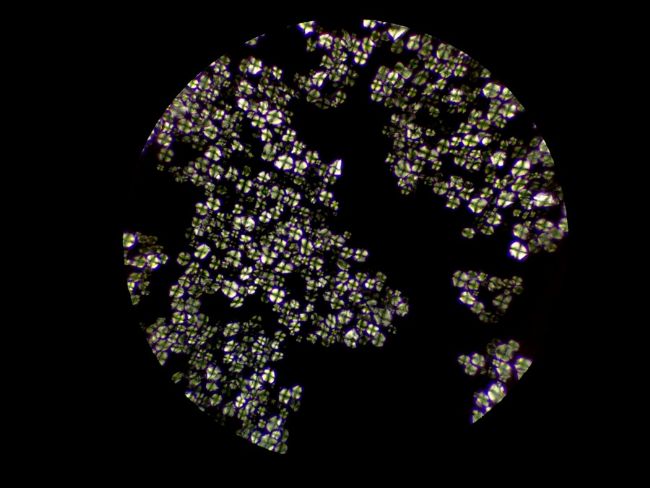

偏光觀察的下中藥粉末

中藥粉末可用生物顯微鏡和偏光顯微鏡進行觀察,中藥粉末包含的草藥栓細胞、導管等結構可用明場型態觀察鑒定,而草酸鈣簇晶和淀粉等成分則可以用偏光觀察鑒定。

中藥顆粒在鏡下可見的成分是淀粉輔料,可在偏光觀察下形成偏光十字,而其有效成分是提取濃縮出來的中藥分子,無法用顯微鏡觀察,需要通過液相色譜等方法才能檢測。